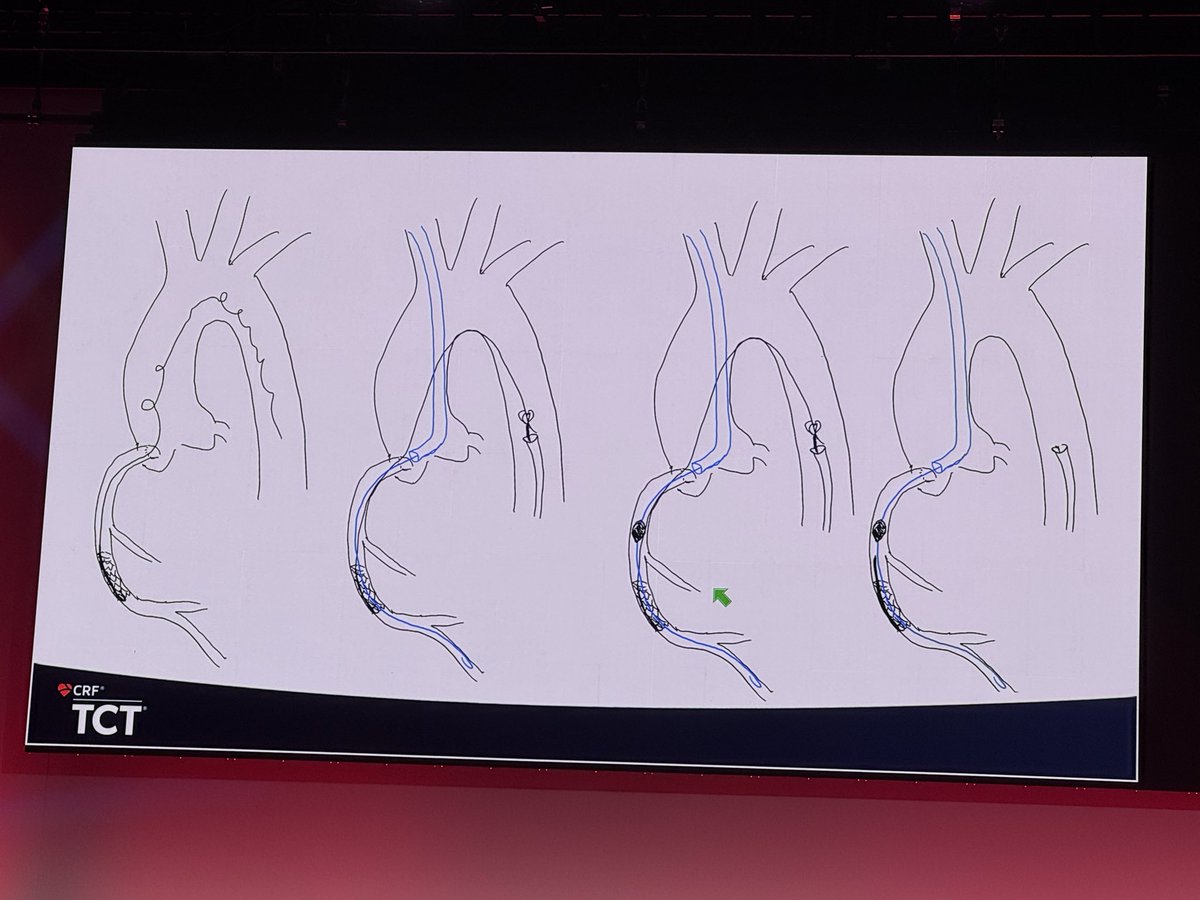

Lost MC tips and unraveled wire, cut with rota!!! #CardioX #CardioTwitter #CardioEd #CardioResearch @BurkhoffMd @djc795 @ColletCarlos @georgedangas @jgranadacrf @MartyBLeon @Drroxmehran @sahilparikhmd @PopmaJeffrey @triciarawh @mirvatalasnag @TCTConference @TCTMD @jedicath…

Lost MC tips and unraveled wire, cut with rota!!! #CardioX #CardioTwitter #CardioEd #CardioResearch @BurkhoffMd @djc795 @ColletCarlos @georgedangas @jgranadacrf @MartyBLeon @Drroxmehran @sahilparikhmd @PopmaJeffrey @triciarawh @mirvatalasnag @TCTConference @TCTMD @jedicath…